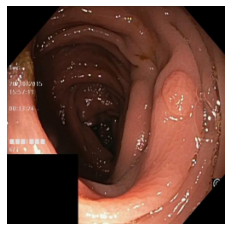

Step 3 prepares the input data in order to produce realistic polyp output from non-polyp colon images. As a simple method, we extract polyp masks and the corresponding edge from the polyp datasets used in Step 2. Alternatively, polyp edge and corresponding masks can be generated using another GAN model. Then, extracted polyp edge is merged into the edge image of a clean colon image.

In Step 4, the edge polyp image returned from Step 3, the corresponding mask, and the clean colon image are provided as input to the pre-trained EdgeConnect model of Step 2. The generated polyp image is the final output of this PolypConnect pipeline. A sample clean-colon image and the generated polyp image generated using it are depicted in Figure 1.